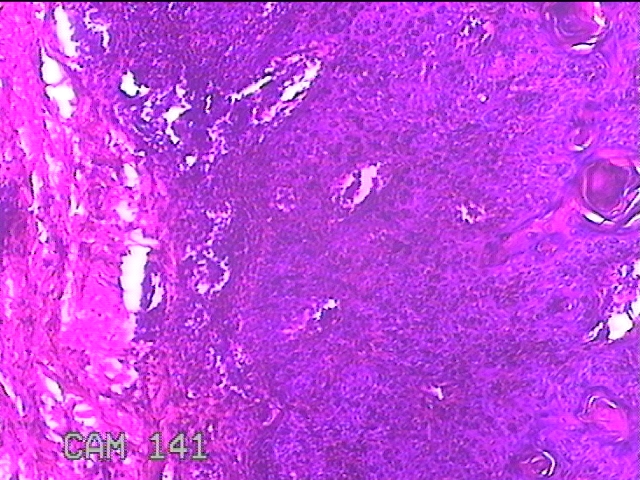

性别

女

年龄

39岁

临床诊断

皮下结节

一般病史

发现左臀部多发性结节5年余。

标本名称

左臀部结节

大体所见

灰白粉红色结节0.7x0.3x0.2cm一个,表面糜烂。

图1